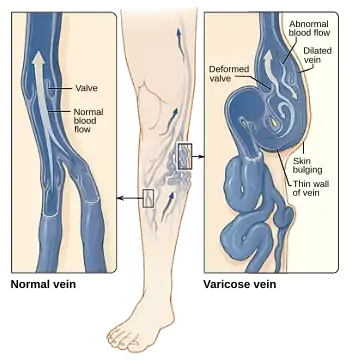

Varicose veins are superficial veins that have become enlarged and twisted.[2][1] Typically they occur just under the skin in the legs.[3] Usually they result in few symptoms but some may experience fullness or pain in the area.[2] Complications may include bleeding or superficial thrombophlebitis.[2][1] When varices occur in the scrotum it is known as a varicocele while those around the anus are known as hemorrhoids.[1] Varicose veins may negatively affect quality of life due to their physical, social and psychological effects.[5]

Often there is no specific cause.[2] Risk factors include obesity, not enough exercise, leg trauma, and a family history of the condition.[3] They also occur more commonly in pregnancy.[3] Occasionally they result from chronic venous insufficiency.[2] The underlying mechanism involves weak or damaged valves in the veins.[1] Diagnosis is typically by examination and may be supported by ultrasound.[2] In contrast spider veins involve the capillaries and are smaller.[1][6]